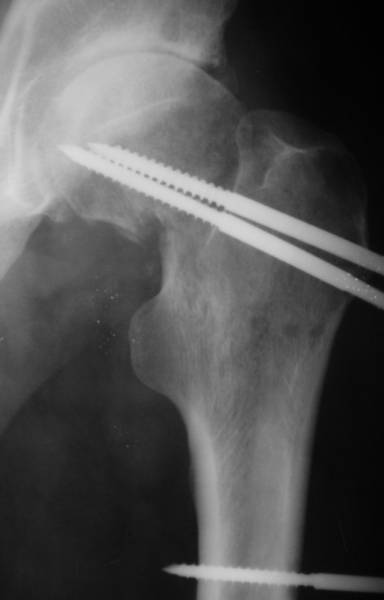

Re: несросшаяся шейка бедра

До травмы проблем с ногой не было. Укорочения, болей и т.п. не отмечал. Сегодня перемерял укорочение - меньше 7 см намерять не

По уровню малых вертелов (с учетом рентгеновского увеличения) получается 5 см. Клинически ногу низвести путем тракции невозможно. Из движений - сгибание до 40*, остальные движения "символические".